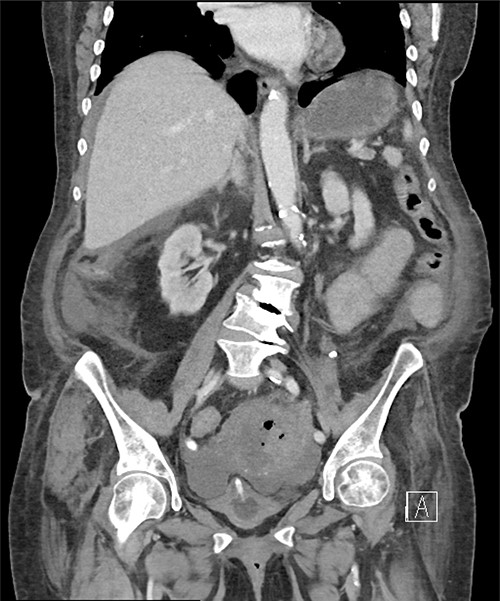

A computed tomography scan revealed significant abdominal ascites and scattered locules of intraperitoneal free air suggestive of a perforated viscous, although no clear gastrointestinal (GI) source was identified (Figs 1 and 2). In addition, evidence of pyometra with possible necrosis and intramural air within the uterine wall was identified. Emergent laparotomy was performed with complete exploration of the peritoneal cavity. The lesser sac was entered, and complete duodenal kocherization was performed, allowing for visualization of the entire GI tract. No GI perforation was identified. A 1-cm defect was seen on the fundus of the uterus with minimal ischaemic tissue surrounding the defect. Purulent material was seen to be emanating from the uterine cavity. The gynaecology service was consulted, and the uterus was assessed via intraoperative hysteroscopy with uterine lavage. Samples were sent for cytology, including uterine effluent and peritoneal fluid. In addition, uterine tissue at the borders of the defect were excised and sent for histopathologic review. All samples ultimately showed no evidence of malignancy.

Pneumoperitoneum demonstrated in the perihepatic and perigastric regions.